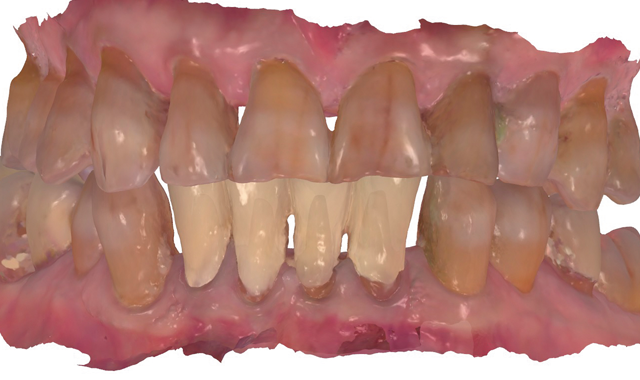

Fig. 2

root surface of the lower incisors-which was visible on the radiograph (Fig. 3)-is known as “Riffle-ization.” Described by Dr. Riffle as a technique for removing every last bit of calculus during repeated root scaling, what is now known as “Riffle-izing," ultimately-over the years-changes the shape of the neck of the tooth to resemble an hour glass.

Therefore, based on the clinical and visual evaluation, the preferred treatment would be to restore the fractured #25 with a post and crown and four splinted crowns to restore the anatomy of the four incisors and increase their resistance to both mobility and fracture.